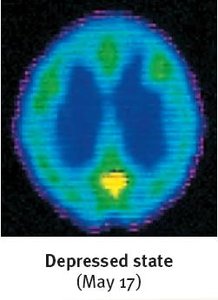

Biological Basis of Mood Disorders

Brain imaging studies show that brain activity is diminished in depression and increased in mania. Structural differences include smaller frontal lobes in depression and fewer axons in bipolar disorder. Neurotransmitter imbalances are also implicated: reduced serotonin in depression and increased norepinephrine in mania.